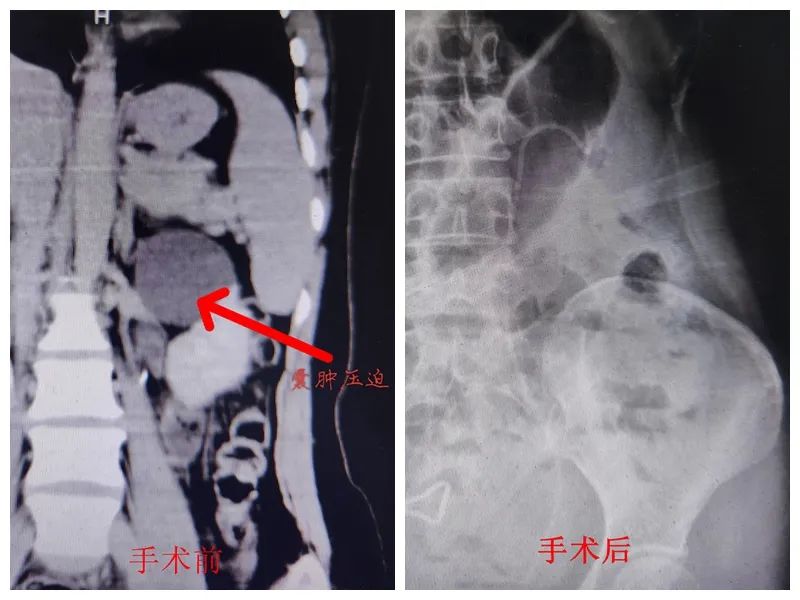

近日,我院泌尿外科成功完成首例肾盂旁囊肿(肾盂内)钬激光内切开引流术,再次刷新泌尿外科微创手术新高度。 据了解,该位患者因腰部胀痛不适半年入院,完善检查后,明确为肾囊肿。肾囊肿是一种常见病,囊肿一般生长在肾脏外面,大于4cm或者出现相关症状时应考虑手术治疗,常用腹腔镜去顶术,手术相对简单。但这位患者的肾囊肿生长在肾脏内部,囊肿压迫肾盂造成肾积水,可继发感染、结石、出血等,由于复杂的解剖关系,在治疗上较为棘手,腹腔镜及开放手术处理起来均较困难,损伤较大、复发率高。 完善相关检查后,随后经科内组织讨论,并与患者及家属进行沟通交流。为达到保护肾脏、减少创伤的目的,最终确定手术方案为输尿管软镜下肾盂旁囊肿钬激光内切开引流术。 手术利用天然腔道进行手术,患者无任何伤口,术中出血仅为粘膜损伤渗血,术后留置输尿管支架管,引流囊液。患者恢复快,损伤小,肾盂囊肿明显缩小,肾脏压迫症状明显缓解,5天后,患者康复出院。